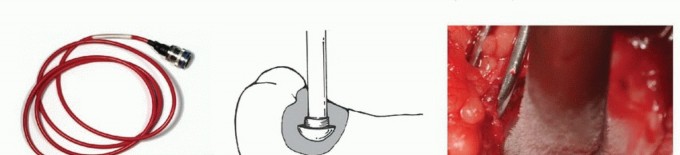

5. العلاج بالتبريد (Cryoablation): النهج الثوري

يُعد العلاج بالتبريد، خاصةً بتقنية الصب المباشر بالنيتروجين السائل، ثورة حقيقية في علاج أورام العظام، حيث يقدم بديلاً فعالاً وآمنًا للجراحات الكبرى، مع الحفاظ على الطرف المصاب ووظيفته. يعتمد هذا النهج على تدمير الخلايا السرطانية عن طريق تعريضها لدرجات حرارة منخفضة جدًا، مما يؤدي إلى تجميدها وموتها.

آلية عمل العلاج بالتبريد:

تتمثل الفكرة الأساسية في تجميد الخلايا السرطانية وتذويبها بشكل متكرر. عند تجميد الخلايا، تتكون بلورات الثلج داخل وخارج الخلايا، مما يؤدي إلى:

تقنية الصب المباشر بالنيتروجين السائل: تفاصيل الإجراء

تعتبر تقنية الصب المباشر بالنيتروجين السائل (Direct Pouring Liquid Nitrogen Technique) في العلاج بالتبريد لأورام العظام من التقنيات المتقدمة التي تتطلب دقة عالية وخبرة جراحية متخصصة. يفضل الأستاذ الدكتور محمد هطيف هذه التقنية نظرًا لفعاليتها في تحقيق تجميد عميق وشامل للورم، مع الحفاظ على الأنسجة السليمة المحيطة.

التحضير قبل الإجراء: